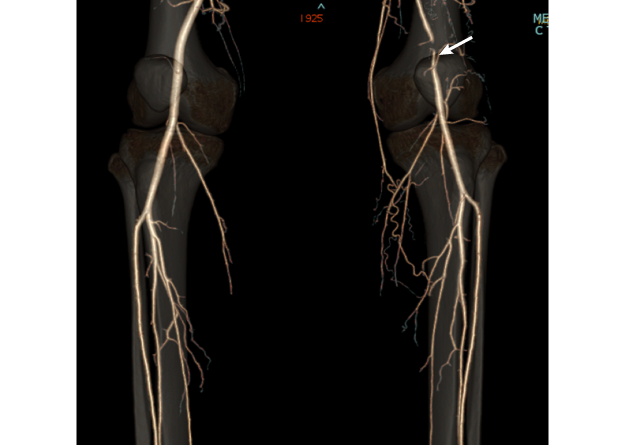

図1

図1. 右膝窩動脈瘤

• 【血管造影所見】膝窩動脈瘤(矢印)

• 【治療】膝窩動脈瘤切除、自家静脈置換術(矢印)